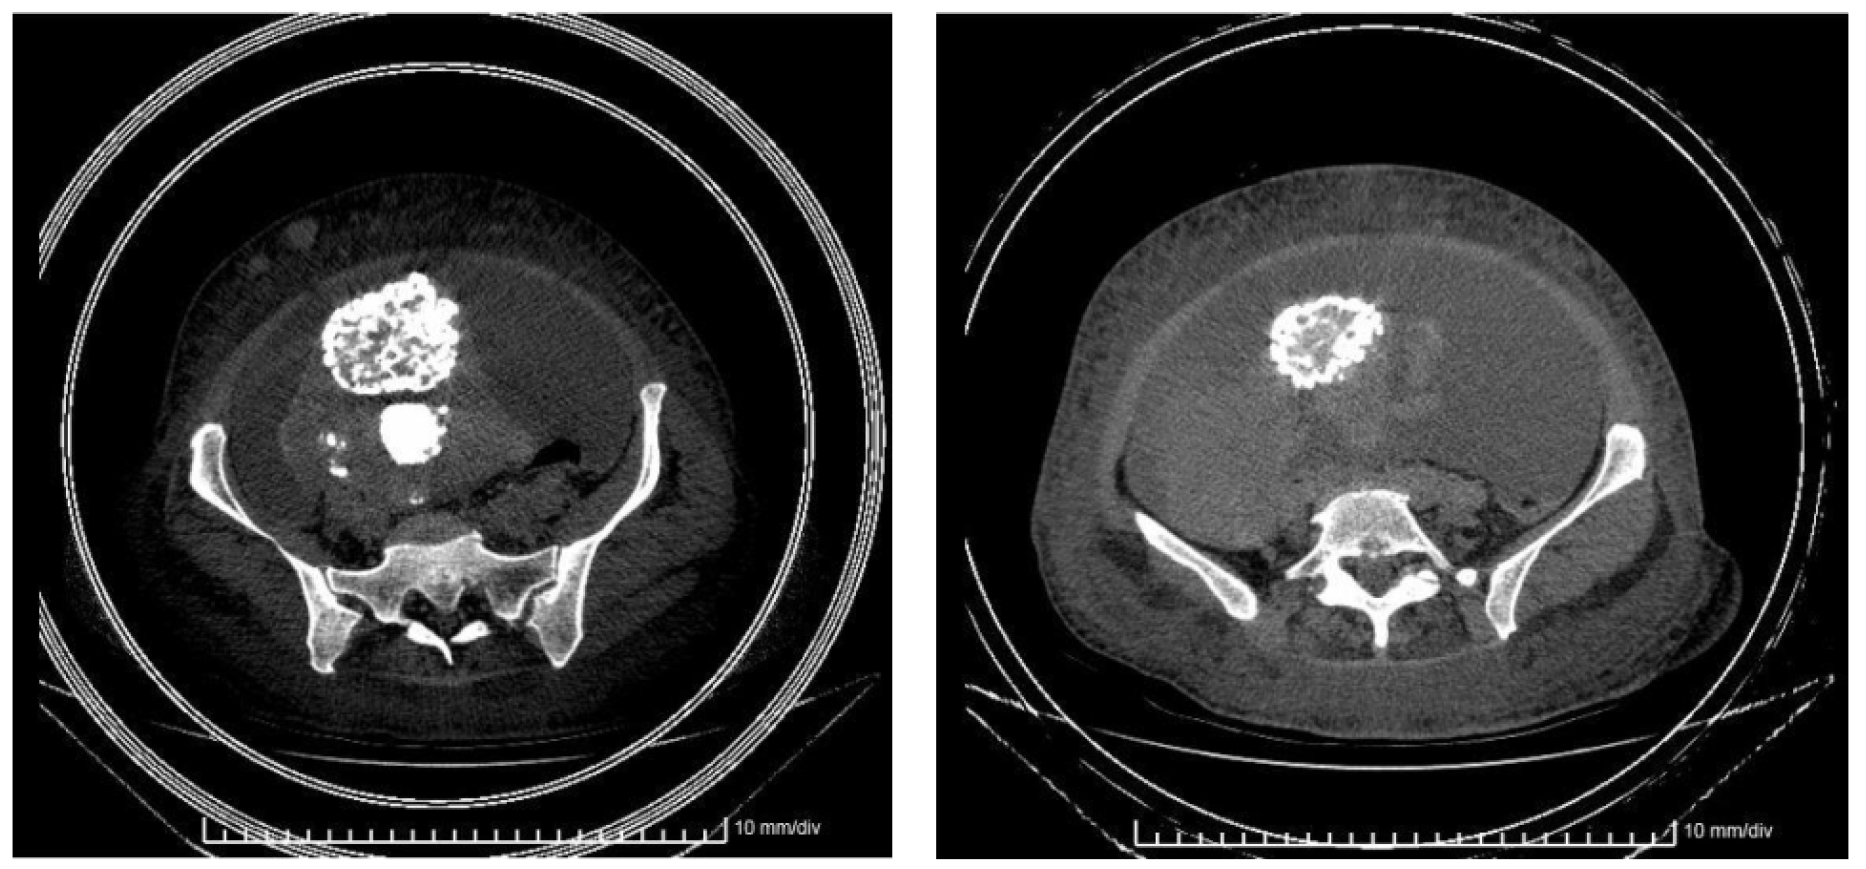

Exámenes diagnósticos: hemograma donde se evidenció leucocitosis de 14.1 x 109/L, hemoglobina de 94 g/L y plaquetas de 225 x 109/L. Además, eritrosedimentación de 40 mm/h, antígeno carcinoembrionario de 0.875 ng/L y CA125 de 1498 U/ml. Una ultrasonografía abdominal total identificó la presencia líquido libre sin definir adecuadamente órganos ginecológicos. También se le realizó una tomografía axial computarizada abdominopélvica que mostró el incremento del tamaño del anejo derecho con calcificaciones múltiples (figura 2).

Figura 2. Tomografía axial computarizada abdominopélvica. Muestra el útero aumentado de tamaño con múltiples miomas calcificados. Hay una masa sólida a la derecha del útero en relación con el anejo derecho; también presencia de gran cantidad de líquido ascítico. Existen varios nódulos en el espesor de la grasa en la pared abdominal; el mayor hacia la región umbilical de 33 mm. Se registra la presencia de adenopatías en las regiones inguinales de aspecto patológico.